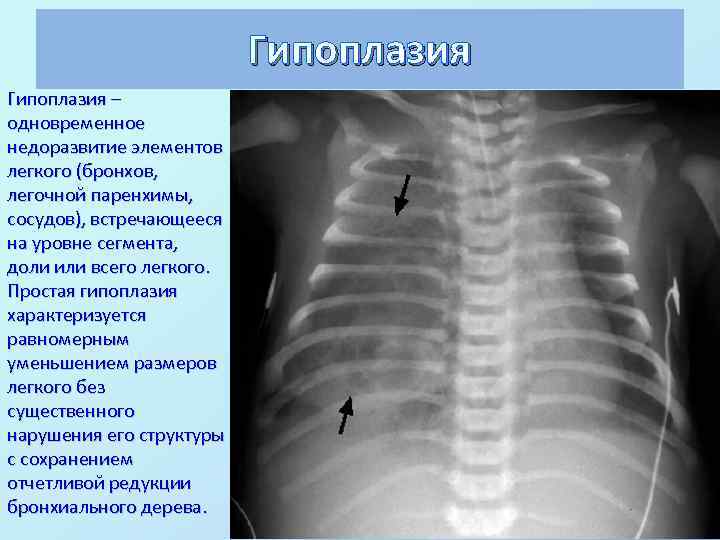

Гипоплазия – одновременное недоразвитие элементов легкого (бронхов, легочной паренхимы, сосудов), встречающееся на уровне сегмента, доли или всего легкого. Простая гипоплазия характеризуется равномерным уменьшением размеров легкого без существенного нарушения его структуры с сохранением отчетливой редукции бронхиального дерева.